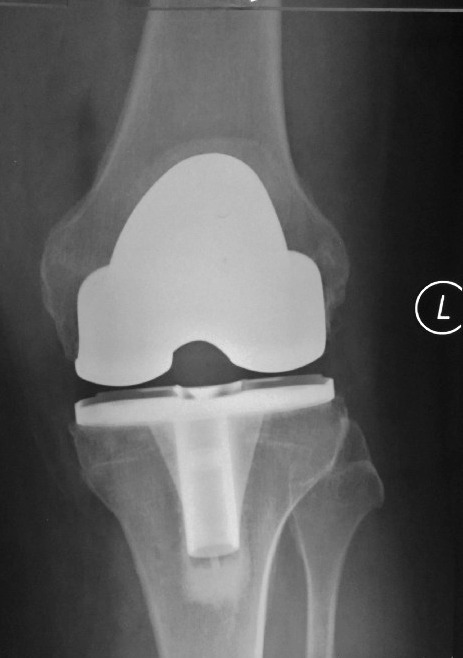

A 60 year old man with painful knee osteoarthritis underwent left total knee replacement using the Zimmer’s iASSIST navigation device.

The check x-rays showed excellent alignment